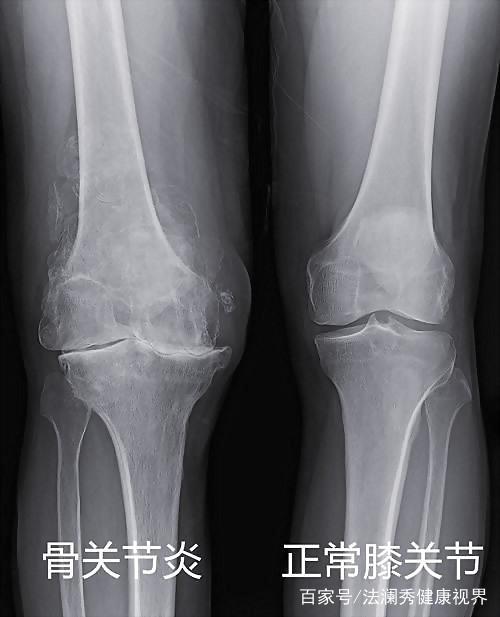

在我的劝说下,堂叔去医院做了X线片检查。

检查结果显示,堂叔右膝盖的关节间隙狭窄,关节面凹凸不平,诊断结果是得了:骨性关节炎。

骨关节炎,又称骨关节病、退行性关节炎、老年性关节炎,是一种退行性病变,主要是以关节退化、磨损引发的疾病,常见有颈椎病、肩周炎、腰椎病、腱鞘炎、滑膜炎等。

像我堂叔,他这个年龄段的人几乎都会患上这种疾病,问题就出在保护骨头末端的软骨上。软骨逐渐被磨损,没有它隔开骨端之间的距离,骨头便会相互摩擦,产生疼痛和僵直感。